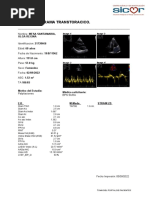

Se le tomaron signos vitales, encontrando lo siguiente:

TA: 75/50 mmHg, FC: 97 lpm, FR: 28 lpm, T: 36.5°C

A la exploración física se observa agitación psicomotora, dificultad respiratoria marcada y

aproximadamente) (figura 5).

Figura 5. Múltiples picaduras de abejas en tórax y abdomen